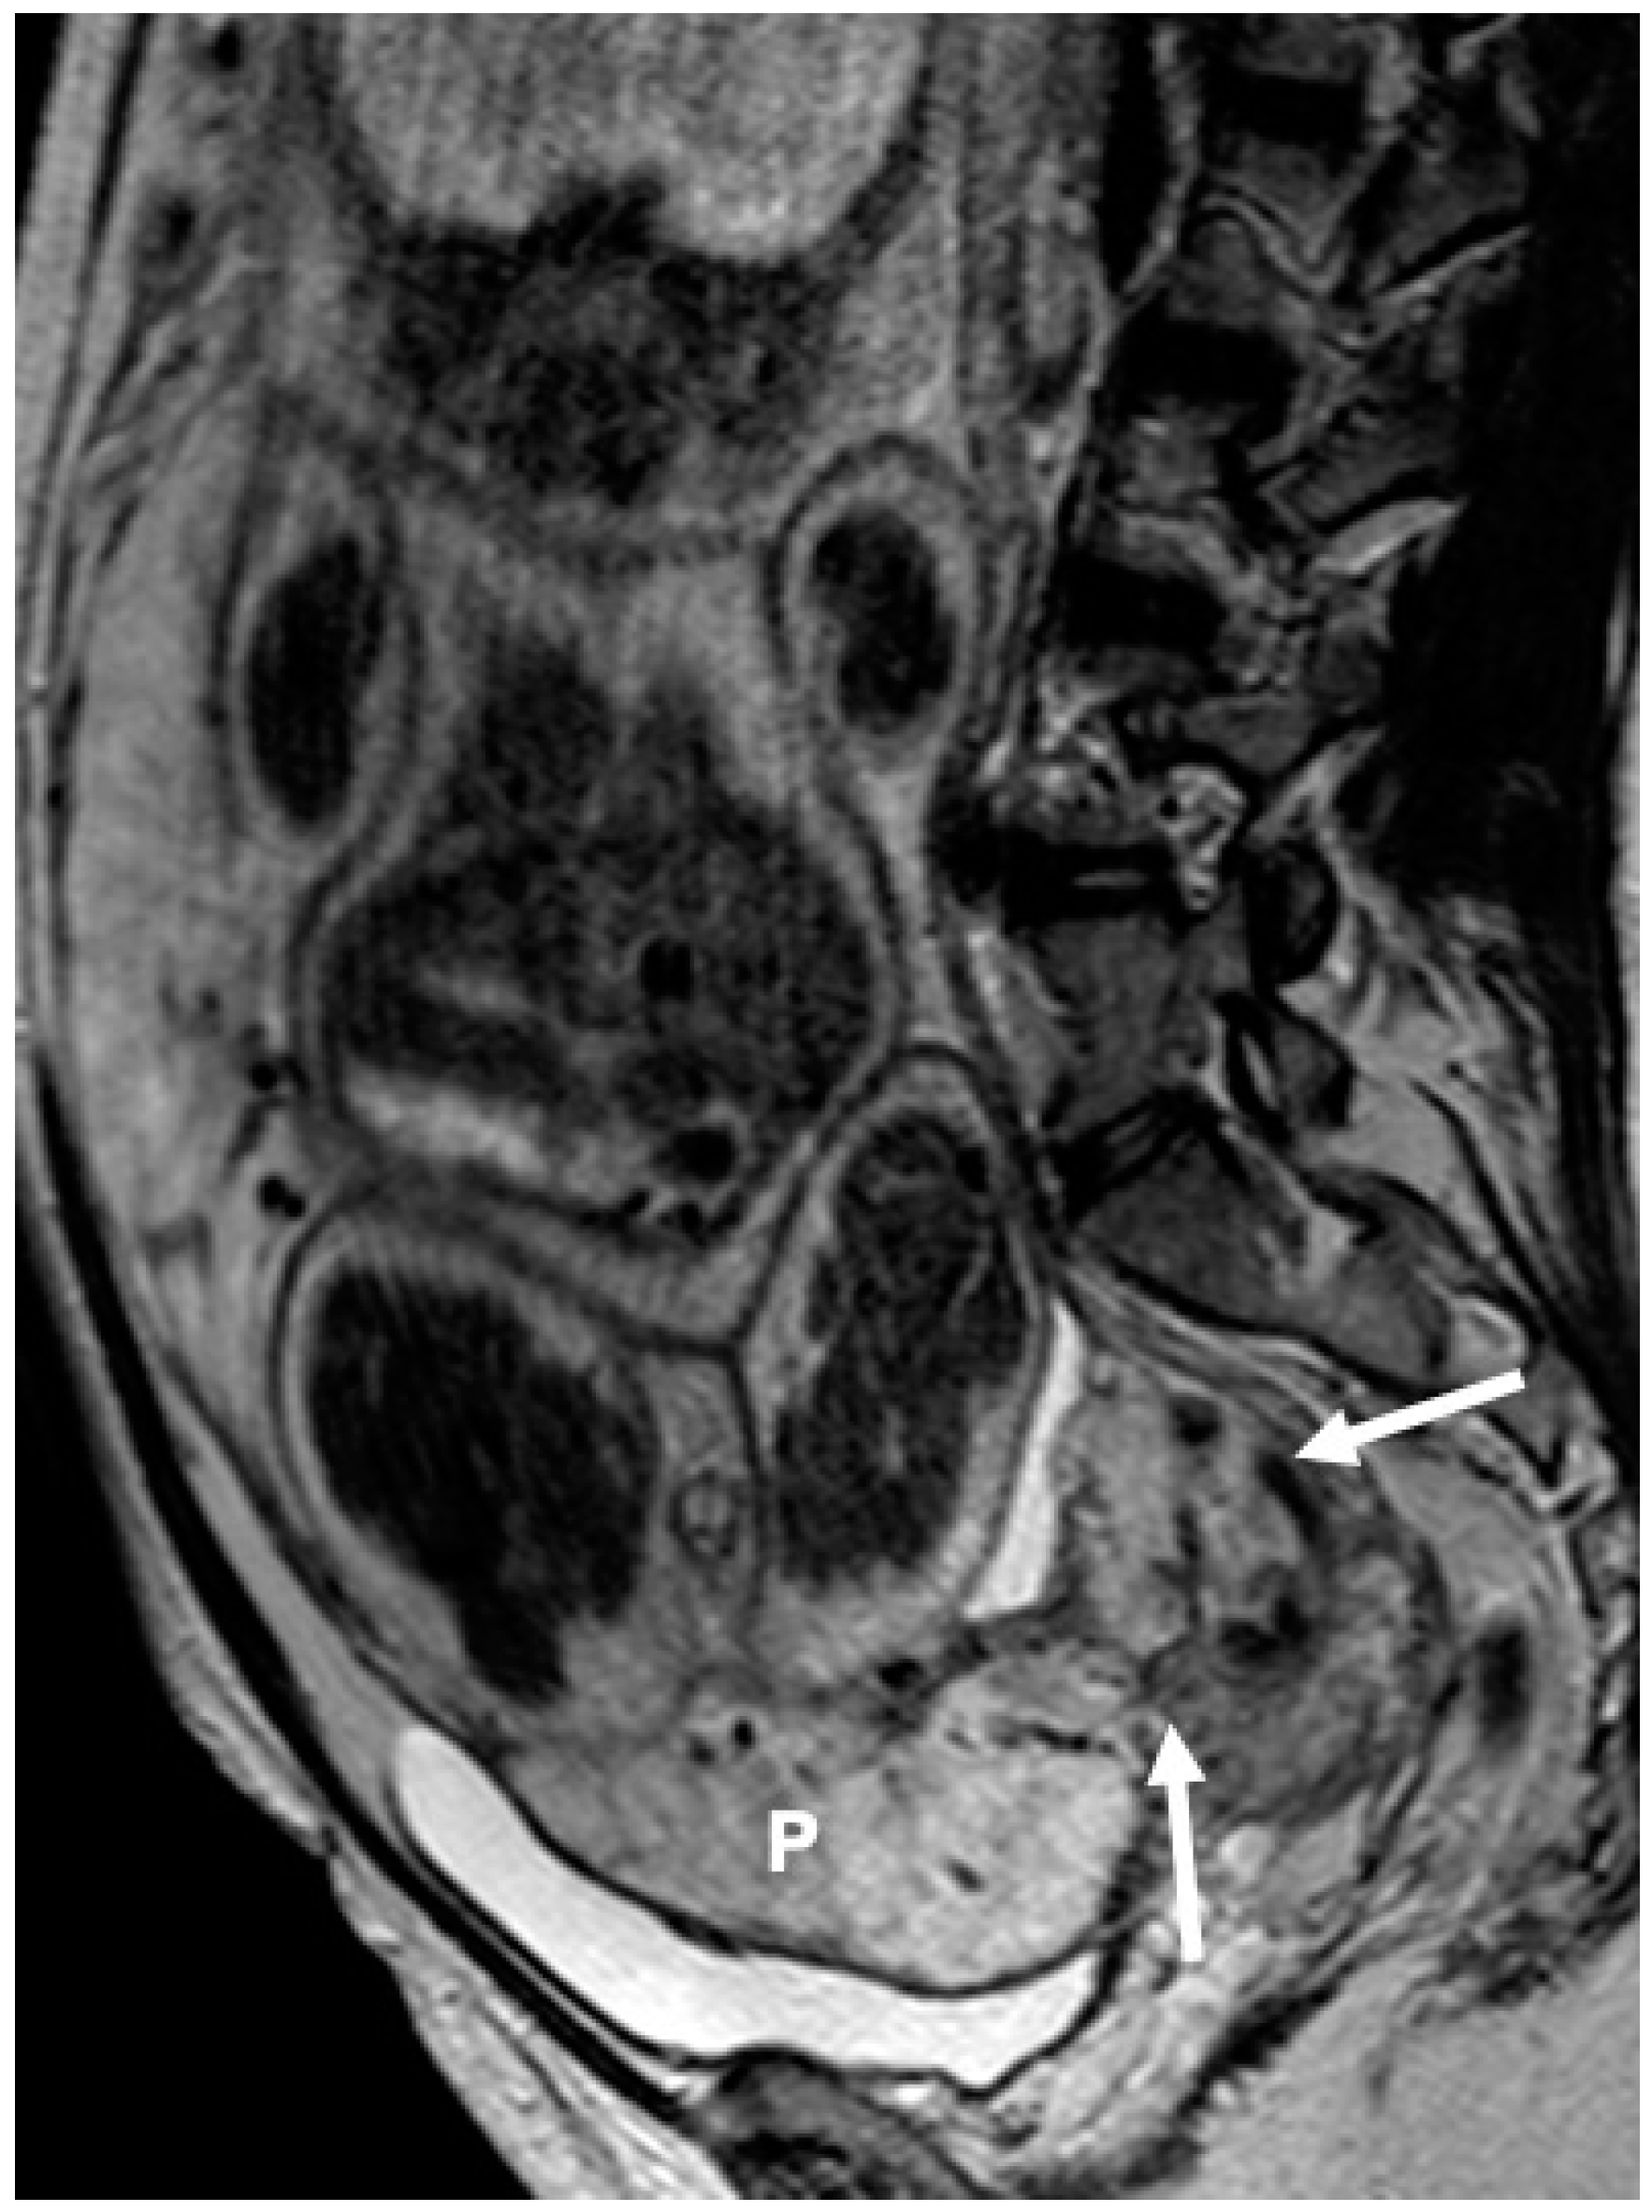

- Bourgioti, C.; Zafeiropoulou, K.; Fotopoulos, S.; Nikolaidou, M.E.; Antoniou, A.; Tzavara, C.; Moulopoulos, L.A. MRI Features Predictive of Invasive Placenta with Extrauterine Spread in High-Risk Gravid Patients: A Prospective Evaluation. Am. J. Roentgenol. 2018, 211, 701–711. [Google Scholar] [CrossRef]

- Bourgioti, C.; Zafeiropoulou, K.; Fotopoulos, S.; Nikolaidou, M.E.; Theodora, M.; Daskalakis, G.; Tzavara, C.; Chatoupis, K.; Panourgias, E.; Antoniou, A.; et al. MRI Prognosticators for Adverse Maternal and Neonatal Clinical Outcome in Patients at High Risk for Placenta Accreta Spectrum (PAS) Disorders. J. Magn. Reson. Imaging 2019, 50, 602–618. [Google Scholar] [CrossRef]

- Bourgioti, C.; Konstantinidou, A.E.; Zafeiropoulou, K.; Antoniou, A.; Fotopoulos, S.; Theodora, M.; Daskalakis, G.; Nikolaidou, M.E.; Tzavara, C.; Letsika, A.; et al. Intraplacental Fetal Vessel Diameter May Help Predict for Placental Invasiveness in Pregnant Women at High Risk for Placenta Accreta Spectrum Disorders. Radiology 2021, 298, 403–412. [Google Scholar] [CrossRef]